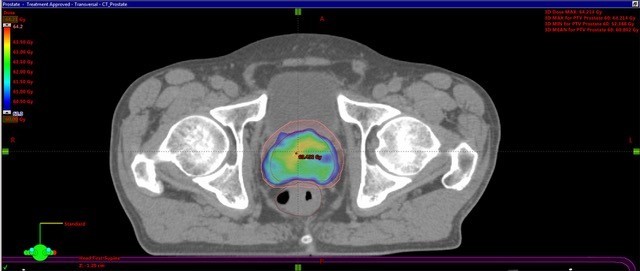

RT in prostate pts - requirements, SE

Need to have a full bladder, empty bowels

SE: skin reaction, fatigue, diarrhoea, tenesmus, cystitis, urinary frequency

What is the GTV, CTV + PTV?

GTV = gross tumour volume CTV = clinical target volume (margin has been added) PTV = Planning target volume (added margin due to patient + tumour movement)